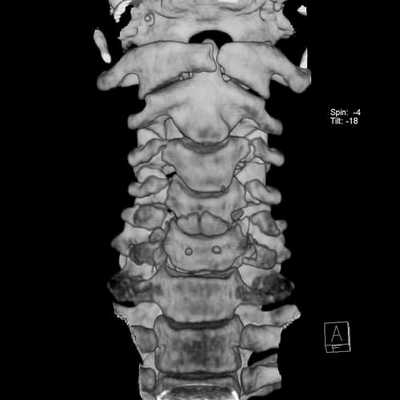

КТ, в отличие от МРТ позвоночника, проводится с помощью небольшого количества рентгеновского излучения. По сути дела, компьютерный томограф - это улучшенный рентгеновский аппарат, позволяющий делать объемные снимки и рассматривать отдельные срезы исследуемой области. КТ наиболее эффективна при диагностике повреждений костных структур и кровотечений. Кроме того, компьютерная томография используется для диагностики сложных травм позвоночника и обследования полых внутренних органов в случаях, когда МРТ провести невозможно.

Что КТ позвоночника покажет лучше, чем МРТ

КТ позвоночника - это приоритетный способ обследования позвонков. Ее следует выбрать, если у пациента:

- произошла травма позвоночника;

- есть перелом позвонков.

Травмы позвоночника включают в себя обширный перечень патологий: ушибы, дистрофии (надрывы или разрывы связок и сумок суставов позвонков без смещения), переломы остистых, поперечных отростков, переломы дуг и тел позвонков, подвывихи и вывихи, травматический спондилолистез. По самому механизму травмы врач уже может предположить, какой участок спины поврежден. Например, хлыстовые повреждения характерны при ДТП, когда происходит резкое сгибание. Также для такого типа нарушений функций позвоночника характерны падения с высоты, травмы ныряльщиков, производственные травмы.

Для точной классификации травмы позвоночника и оценки ее последствий врачу необходимо сделать КТ.